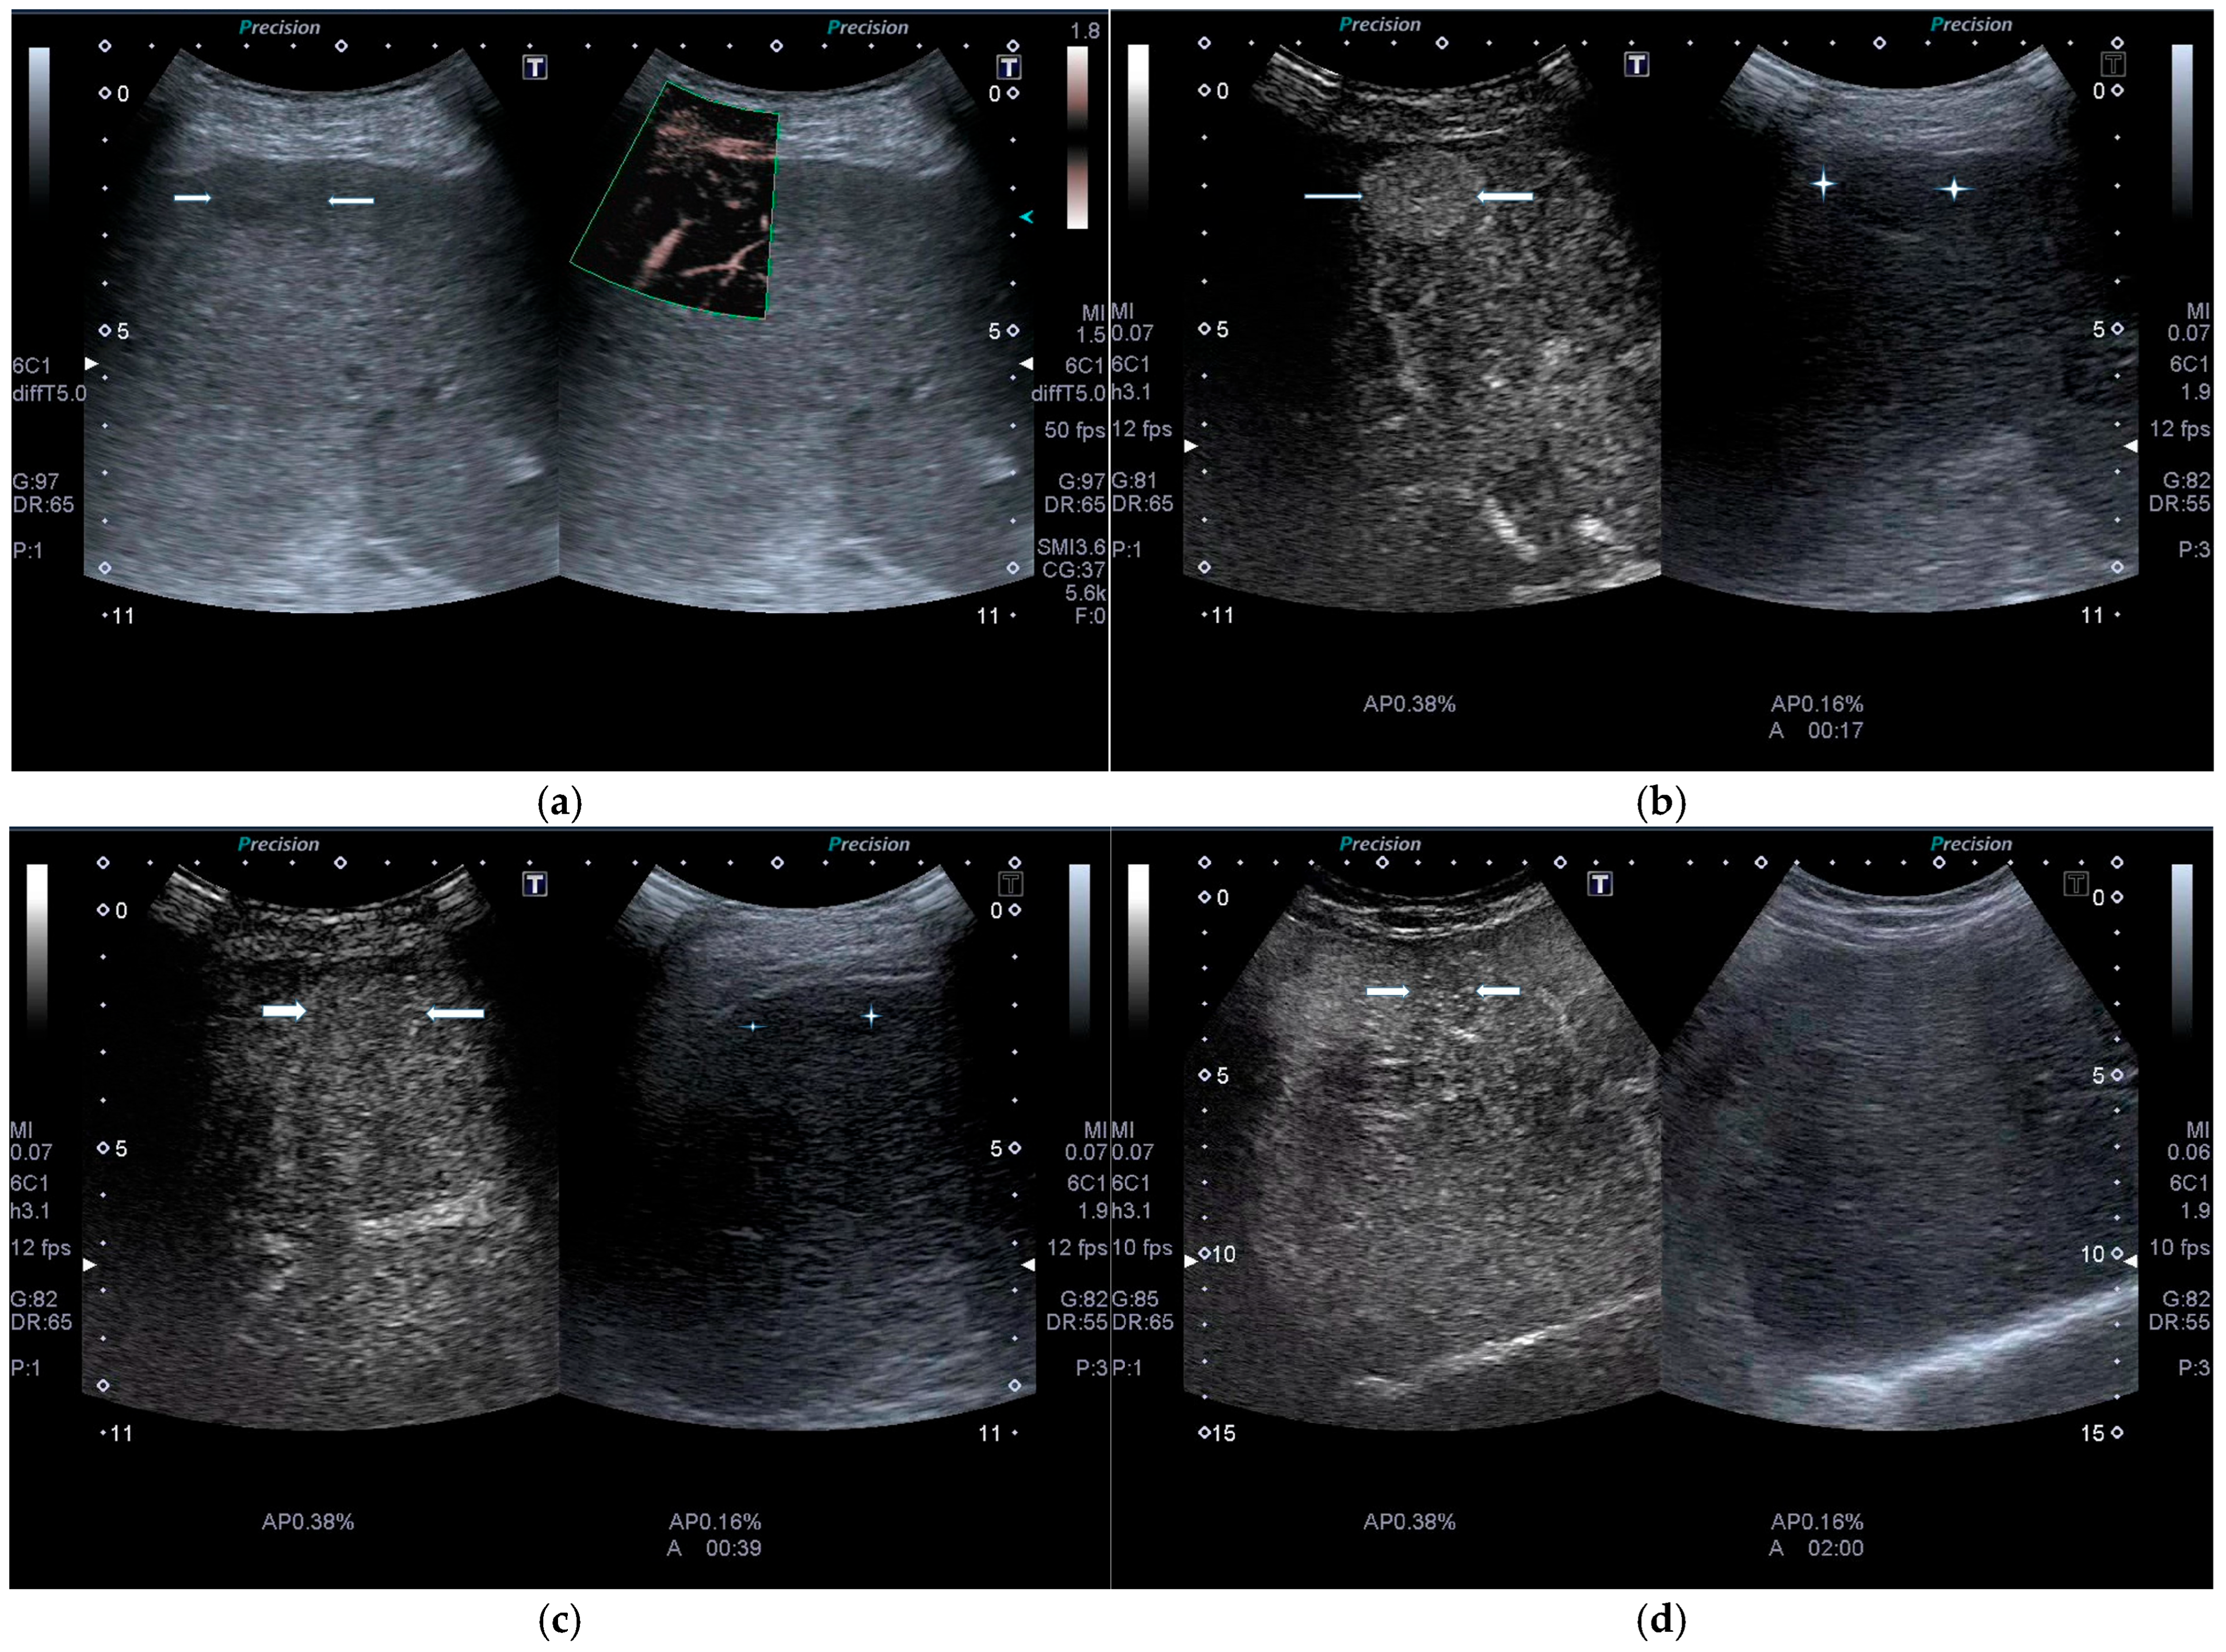

| POST-VIRAL HCC | MASLD HCC |

|---|---|

|

| |

| These characteristics would be focused more on the lack of malignancy rather than HCC. | |